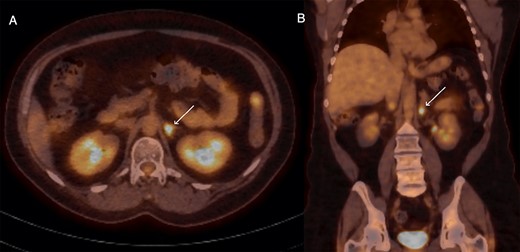

Surveillance fluorodeoxyglucose positron emission tomography (FDG-PET) demonstrated a new focus of FDG avidity in the left adrenal gland (Fig. 1). The adrenal lesion was not symptomatic or functional. Magnetic resonance imaging (MRI) of the adrenals did not demonstrate any lesion in the left adrenal gland. The case was discussed, and a joint multi-disciplinary decision was made to proceed with adrenalectomy in lieu of concerns regarding cumulative radiation exposure, and to leave radiation therapy options open in case of future disease recurrence. Pre-operative biopsy was not undertaken due to the risk of complications and due to the fact that a negative result would likely not have changed the course of management, a position echoed by a series reporting a complication rate of 13.6%, and concluding that needle biopsy did not alter clinical management in any of their patients [3].

Axial (A) and coronal (B) sections of FDG-PET demonstrating glucose-avid lesion in the left adrenal (arrow).